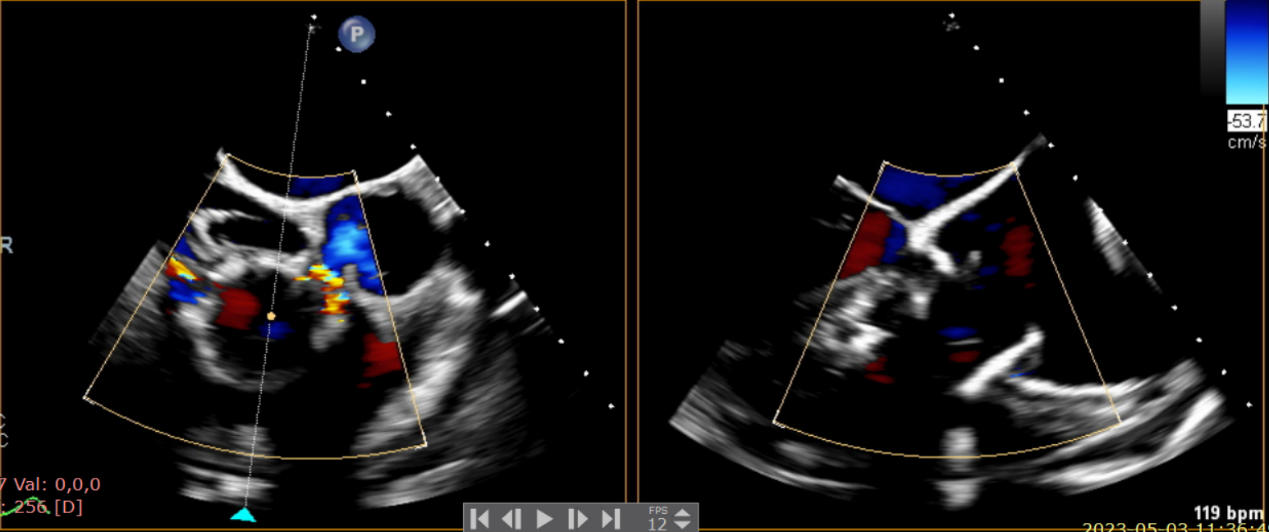

術(shù)前超聲提示大量三尖瓣反流

術(shù)中輸送器在超聲引導(dǎo)下調(diào)整位置

術(shù)后超聲提示僅殘余輕微瓣周漏